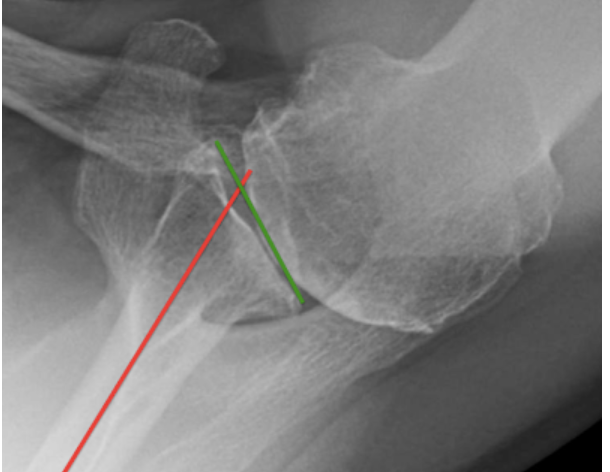

Some surgeons contend that – when performing aTSA – it is important to insert the glenoid component in 15 degrees or less retroversion. This is accomplished by eccentric reaming of the anterior glenoid bone, use of a posteriorly augmented glenoid component, or both. As shown below, this approach can come at the cost of removing robust glenoid bone,

And in this set of x-rays obtained 10 years after surgery